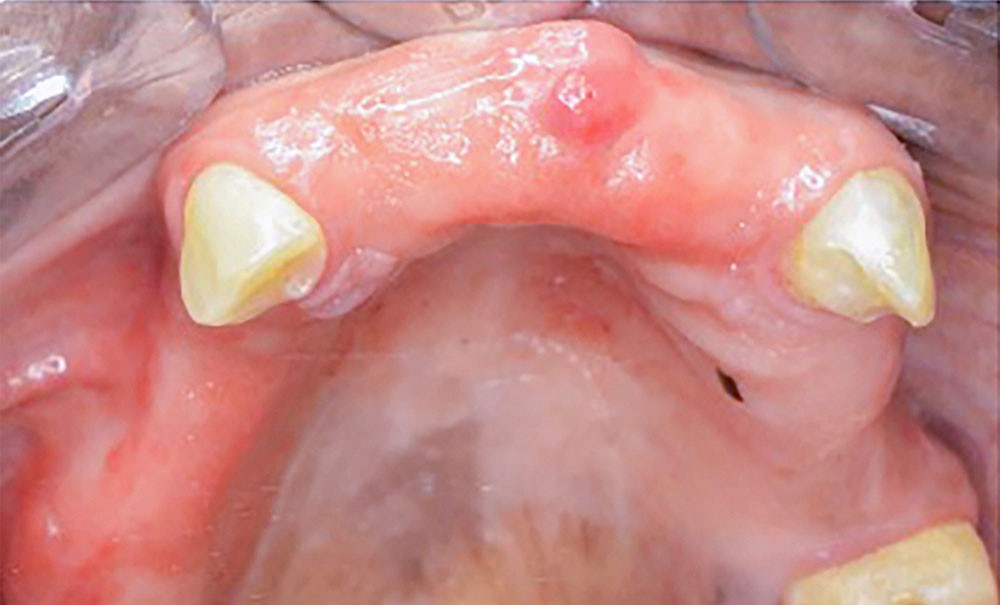

En Côte d’Ivoire, les édentements sont compensés par les prothèses amovibles.Mais leur caractère amovible a des conséquences sur la fonction orale et le psychisme du patient.

Apprécier l’influence de certaines variables sociodémographiques et cliniques sur les domaines de la qualité de vie orale (QVO) des porteurs de prothèse amovible venus au service de prothèse clinique du Centre de consultation et de traitements odonto-stomatologiques (CCTOS) d’Abidjan pour une prise en charge.

Dans cette étude transversale ont été inclus 240 patients âgés de 39 à 73 ans avec au moins une prothèse amovible (PA) de moyenne portée (5 dents minimum). Tous les participants ont répondu au questionnaire issu de la synthèse de OHIP 20 (Oral Health Impact Profil) et du GOHAI (Geriatric Oral Health Assessment Index) avec des scores allant de 1 à 5 (plus le score est élevé moins est bonne la QVO). Après une modélisation par régression logistique des scores, les corrélations entre les variables qualitatives de la QVO et des caractéristiques sociodémographiques et cliniques ont été calculées avec le test de KHI-2 (p < 0,05).

Les sous-scores de la limitation fonctionnelle, de la douleur physique, de l’incapacité physique et l’incapacité psychologique sont très élevés. Cependant l’inconfort psychologique qui comporte la composante esthétique a un sous-score moins élevé. Les femmes (25 %) ont une QVO plus altérée que les hommes (50 %). Les patients plus jeunes (60 %) ont exprimé une meilleure QVO que les patients âgés. En outre, il n’existe pas de lien statistiquement significatif (p > 0,05) entre la QVO, le genre, l’âge et la classe socioprofessionnelle. Concernant les caractéristiques cliniques, les porteurs de prothèses non rétentives ont paradoxalement une meilleure QVO. En même temps, il n’existe pas de lien statistiquement significatif (p > 0,05) entre la QVO, la rétention/stabilité des prothèses, la portée de l’édentement, la fréquence de port et les antécédents prothétiques.